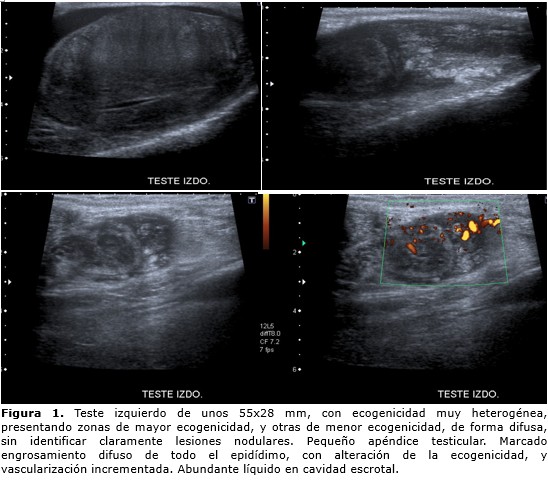

Paciente de 55 años, antecedentes de ser fumador cinco cigarrillos/día, bebedor ocasional, hipertensión arterial en tratamiento con olmesartan 20mg/día. Acude a consulta por presentar aumento del volumen del hemiescroto izquierdo de un año de evolución. A la exploración física en la inspección impresiona un hidrocele, pero a la palpación presenta teste izquierdo aumentado de tamaño, indurado, tacto rectal se palpa una próstata aumentada de tamaño, superficie regular, bien delimitada, fibroadenomatosa G-II. En la analítica el hemograma, leucograma, marcadores testiculares: β-HCG, CEA, AFP, función renal, hepática y pancreática normales, aumento de la lactato deshidrogenasa (LDH). Se le realiza ecografía escrotal y testicular que informa: Teste derecho de unos 47x15 mm, sin identificar alteraciones patológicas significativas del epidídimo. Teste izquierdo de unos 55x28 mm, con ecogenicidad muy heterogénea, presentando zonas de mayor ecogenicidad, y otras de menor, de forma difusa, sin identificar claramente lesiones nodulares. Marcado engrosamiento difuso de todo el epidídimo, con alteración de la ecogenicidad, y vascularización incrementada. Abundante líquido en cavidad escrotal (Figura 1).

figura 1